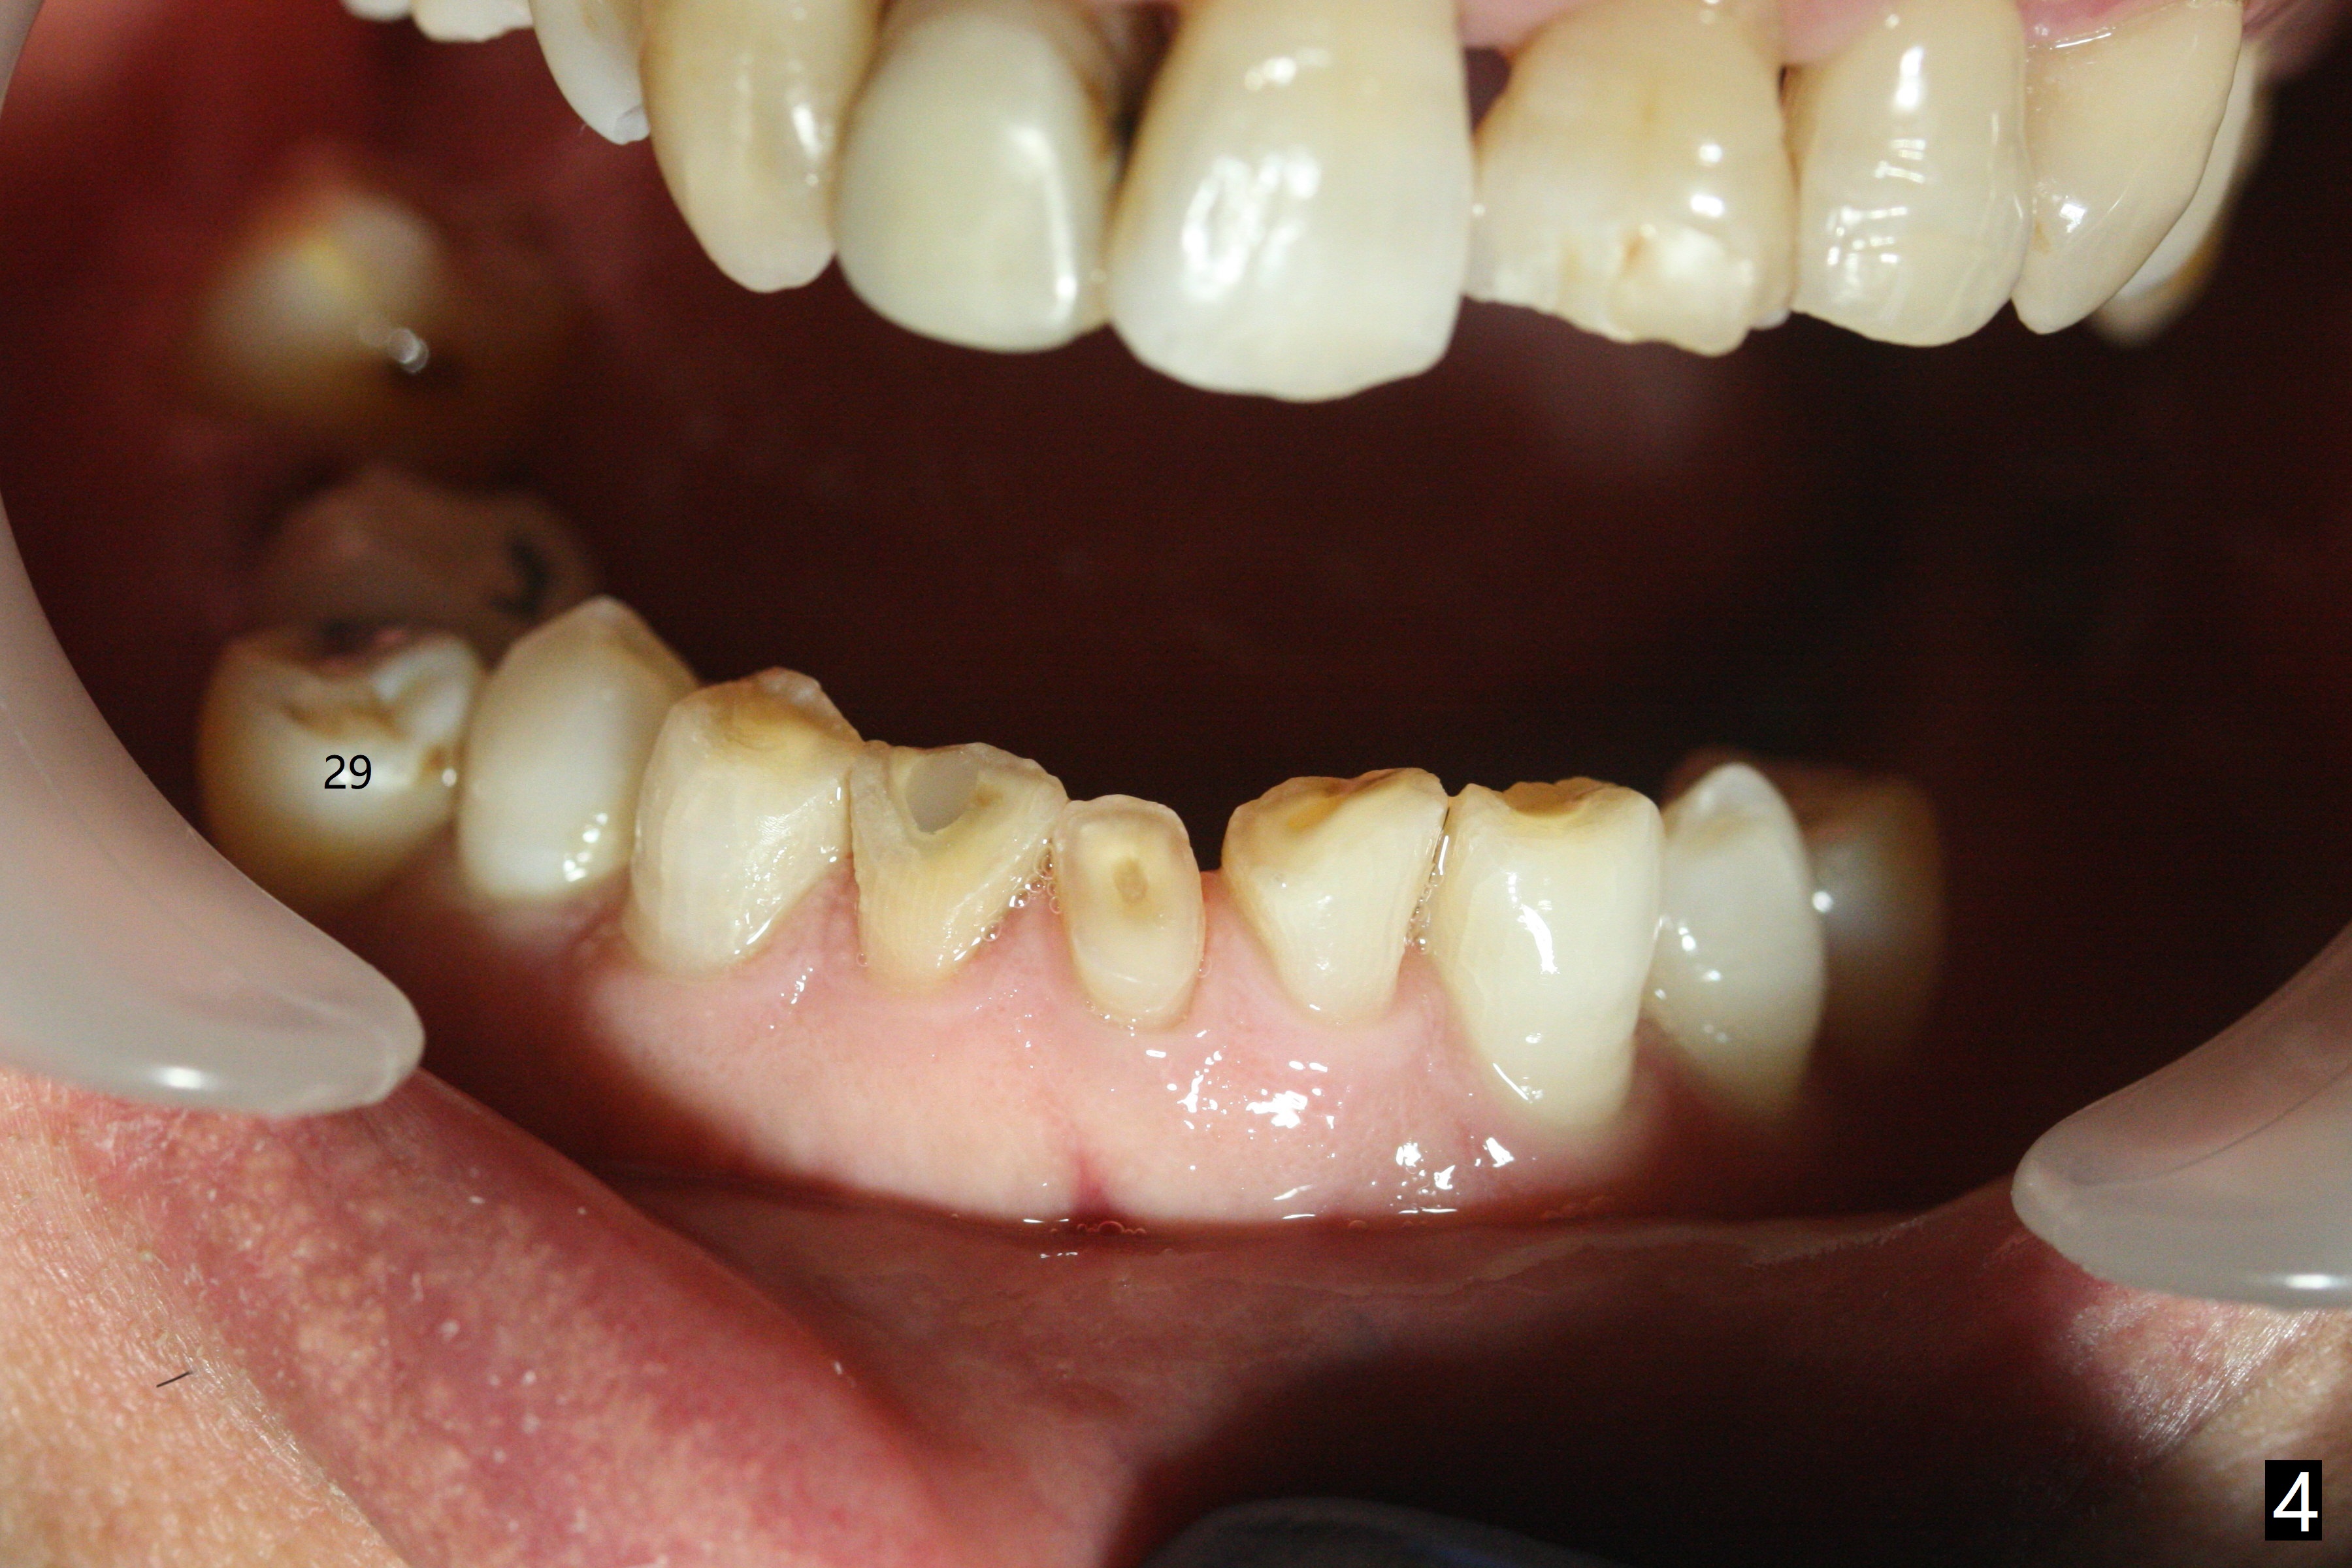

A 61-year-old man presented to clinic for new patient examination last year (Fig.1). He was not interested in extraction and implant at #30 because of finance. This year he requested treatment since he cannot chew well (Fig.2). After exam, extraction and implant at #30 appear not to be a priority, since there is anterior deep bite (Fig.3) with posterior occlusal collapse (Fig.4) as well as #29 malposition.